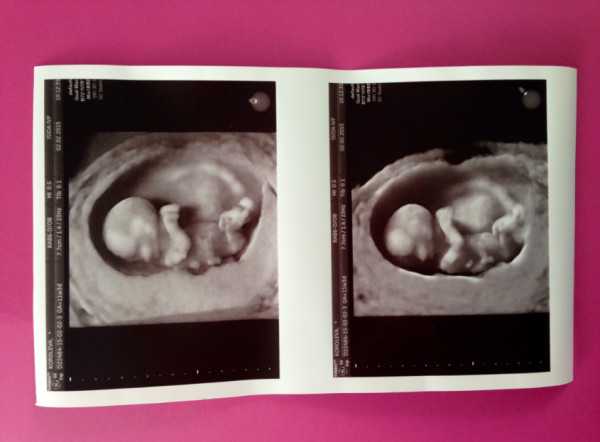

- Если говорить о плановом УЗ-скрининге 1 триместра, то он проводится у всех беременных в примерно одинаковое время — в 12-13 недель. Такой период определен не случайно: именно в этот промежуток есть шанс узнать достоверную информацию о состоянии здоровья малыша. Врач уже увидит очертания лица, груди и животика. На фото хорошо просматриваются конечности, а на современном оборудовании четко видны пальчики.

Обязательный момент – обследование сердца со звуком его биения. Врач измеряет не только размер и вес ребенка, но и КТР (размер от копчика до темени), БПР (бипариентальный размер головки), длину носовых костей и ТВП (толщину воротникового пространства). Это необходимо для выявления генетических отклонений.

Во время УЗ-скрининга записывают видео и делают фотографии в формате 3D, которые остаются на память родителям. К тому же можно узнать пол ребенка. Установить, кто находится в утробе, — мальчик или девочка, можно в том случае, если исследование проводится на высокоточном оборудовании и имеется удобный ракурс. Однако при определении пола ребенка существует вероятность ошибки.

12 неделя беременности – важное время для будущей мамы. Именно в этот период проводится первое скрининговое обследование, позволяющее оценить внутриутробное развитие плода. Пройдя комплексную диагностику в конце первого триместра, беременная получит полную картину, характеризующую состояние ребенка и фото УЗИ, которое многие с удовольствием вкладывают в семейный альбом. А для врача результаты исследования будут надежным руководством в составлении дальнейших рекомендаций.